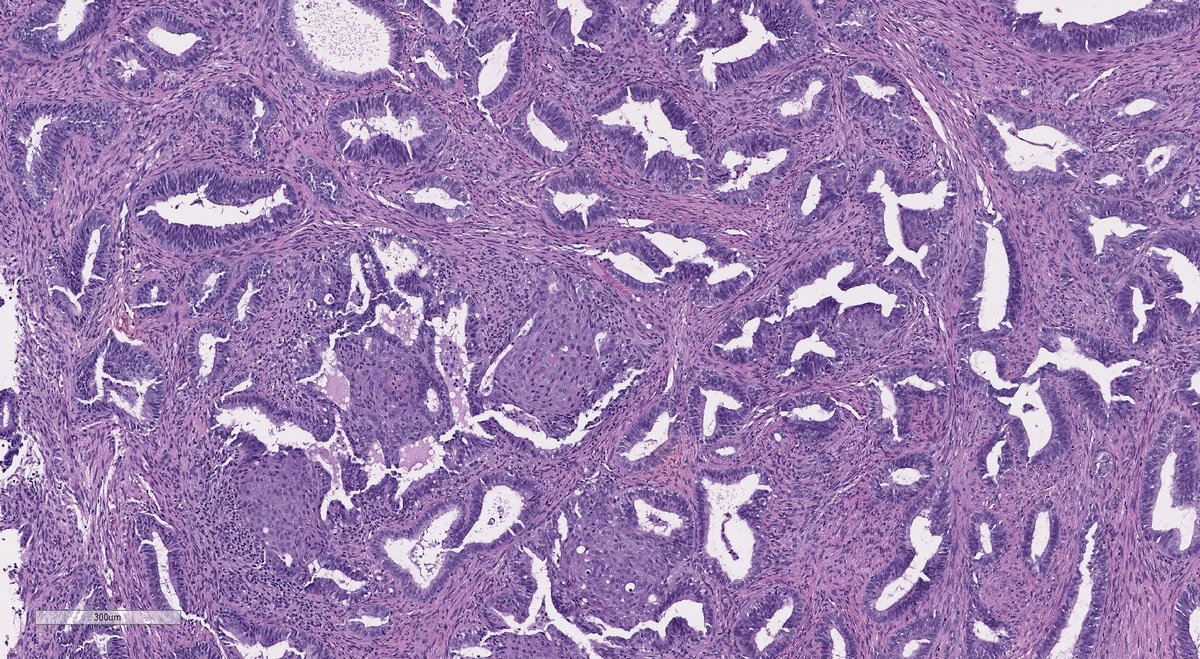

After a long Twitter hiatus because... life... I'm back to bring you this endometrial lesion in a 42 yo woman with abnormal uterine bleeding. Hysteroscopy showed an endometrial polyp in the lower uterine segment #GynePath #GynPath #PathTwitter